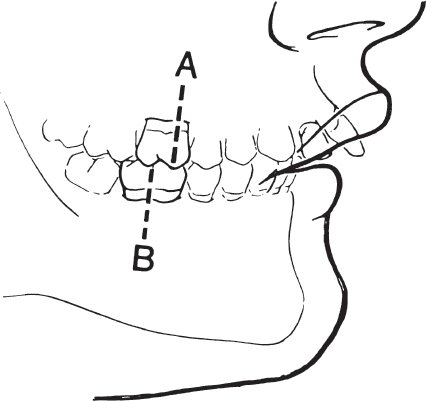

Class II malocclusion is skeletally and dentally based. The mesial buccal cusp of the first maxillary molar is mesial, or in front of the first mandibular molar ( Fig. 70.3 ).